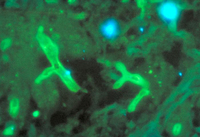

Mucormicose

Rhizopus arrhizus evidenciado em imunofluorescência

Da CDC Public Health Image Library (PHIL): Dr William Kaplan